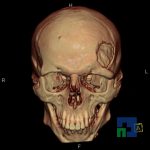

În cazul traumatismelor cranio-cerebrale:

- Diagnosticul traumatismelor de bază de craniu

- Diagnosticul fracturilor:

- Complexe cranio-sinusale

- Complexe cranio-etmoidale

- Complexe cranio-orbitare

- Complexe cranio-faciale